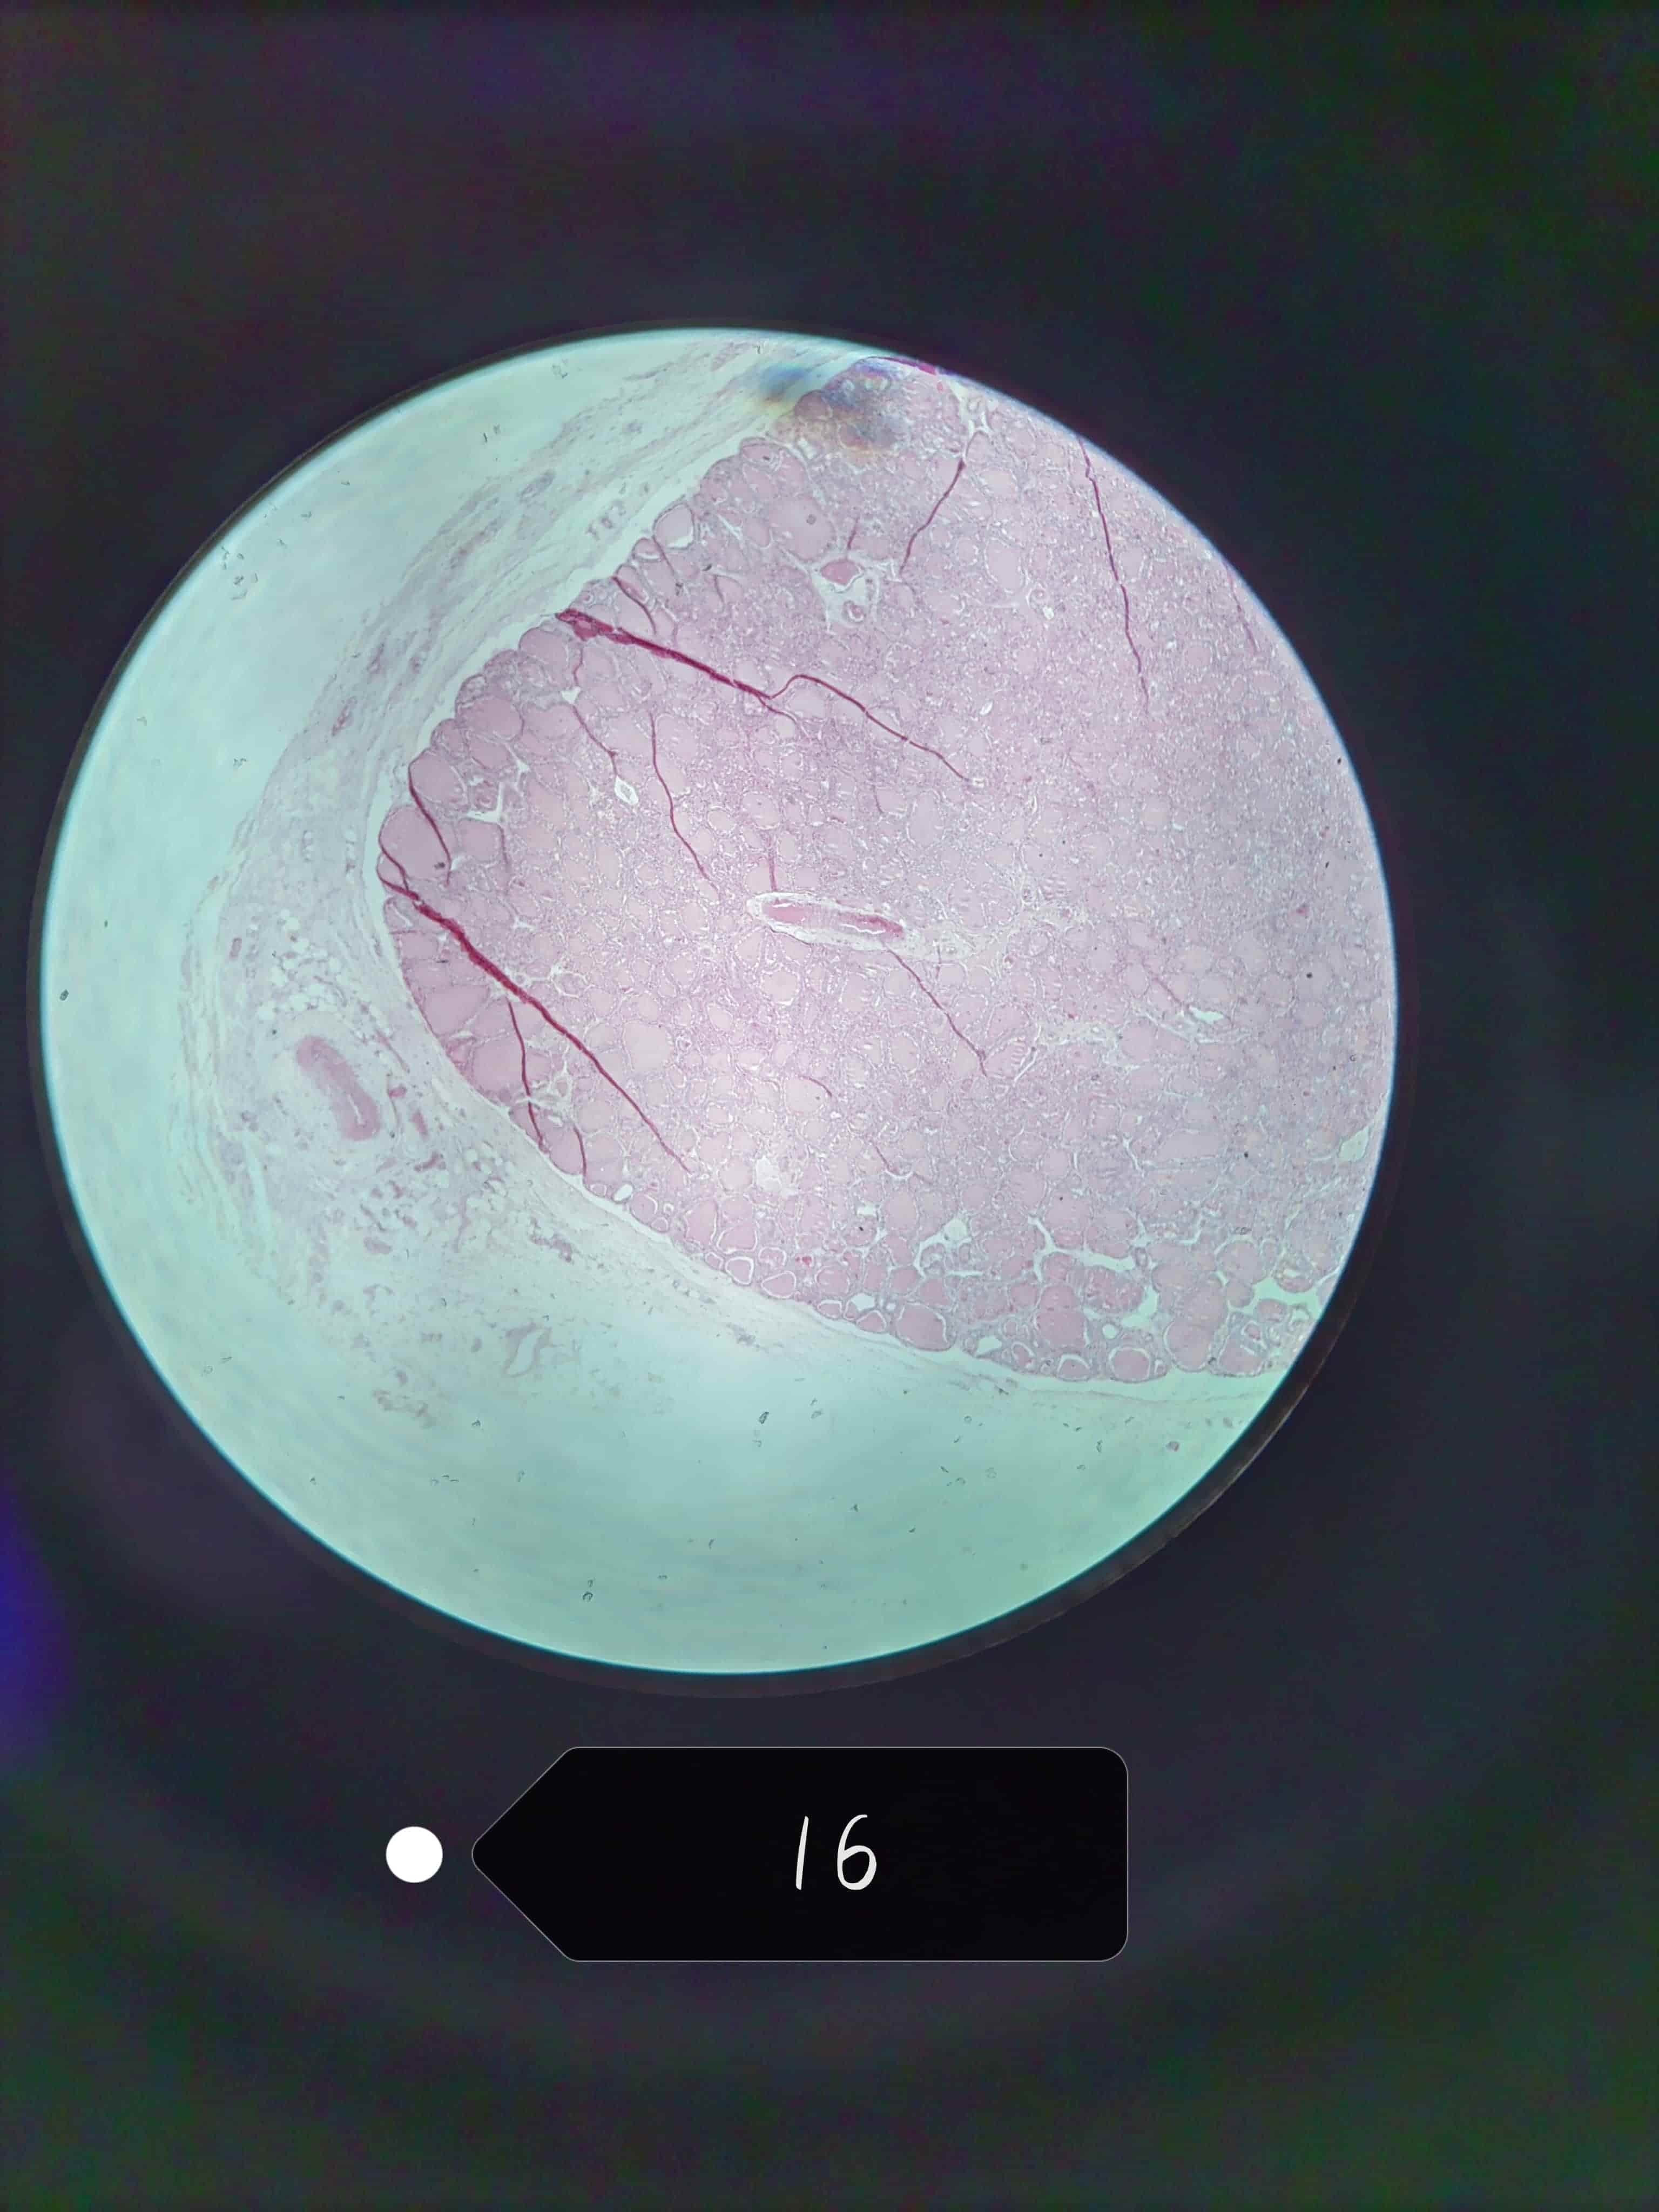

卵巢

周围部分较厚可见大小不等的卵泡

初级卵母细胞和卵泡细胞之间有透明带